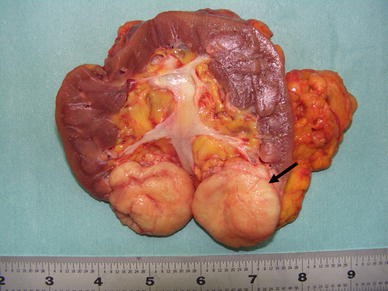

Macroscopic findings of the resected kidney revealed a well-demarcated tumor in the lower portion. The tumor had a yellowish-white cut surface (arrow)